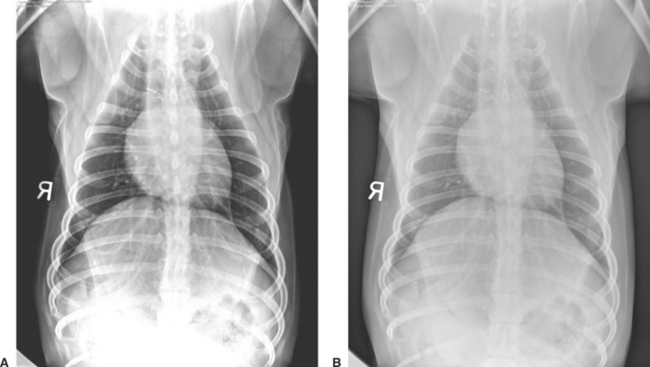

The higher-contrast resolution (or exposure latitude) of digital radiography has several tremendous advantages over conventional screen-film radiography. The need for retakes resulting from overexposure and underexposure is reduced, and for the most part eliminated. Images that are too light or dark that would be discarded on radiographic film can be adjusted with the digital image management software (Fig. 22-4). Marginal radiographic images, which may have previously been deemed acceptable, are a thing of the past.

Figure 22-4 Lateral thoracic radiographic image of a cat illustrates how overexposure (A) and underexposure (B) can be image processed to produce a perfectly exposed image (C). With conventional film-screen radiography, the improperly exposed studies would require retaking the radiographs.